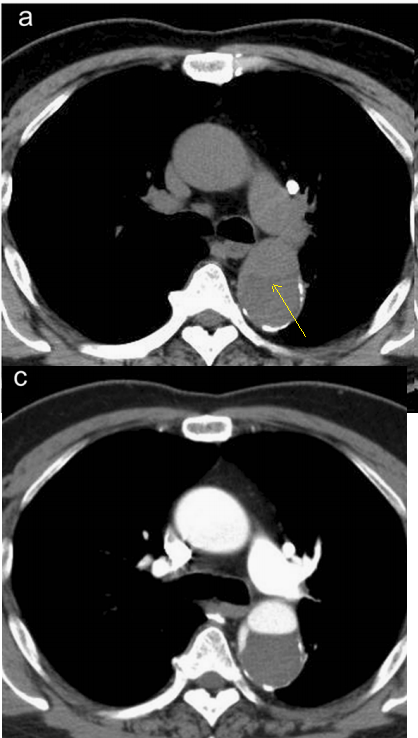

赞!这些夹层,光看ct平扫也能发现